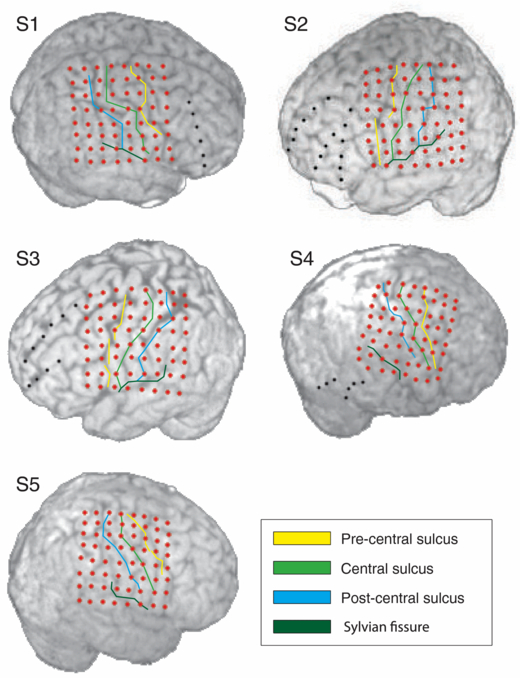

For pre-neurosurgical epilepsy diagnostics, the subjects were implanted with an 8 × 8 grid of subdural surface electrodes (Ad-Tech, Corp., 1 cm inter-electrode distance, 4 mm electrode diameter) covering parts of the primary and pre-motor cortex (figure 1). S1, S2, S3 and S4 had additional ECoG stripes implanted. In addition to the signal from the subdural electrodes, 21 surface EEG channels, one or two bipolar electro-oculography (EOG) channels, the electrocardiography (ECG) channel and several electromyography (EMG) channels were recorded. Signals from the ECoG electrode stripes, EEG, ECG and EMG channels were not analyzed in this study.

Figure 1. Position of the implants on the neocortex and in relation to the Sylvian fissure, precentral, central and postcentral sulci. Brain outlines were reconstructed from the pre-implantation MRI of the subjects. Electrodes (red and black dots) and sulci were reconstructed from the post-implantation MRI of the subjects. Note that, due to local pressure in the region of the implant, brain tissue can be partially compressed and the brain surface can be slightly deformed relative to the pre-implantation state. Therefore, a mismatch between the sulci on the pre-implantation MRI and sulci reconstructed from the post-implantation MRI is possible. We analyzed the signals from the electrode grid implants only (red dots).

Standard imageData from post-implantation MRIs were used to reconstruct the positions of the Sylvian fissure, central sulcus, postcentral sulcus and precentral sulcus with respect to the electrodes (figures 1 and 3). The reconstruction informed us whether an electrode was lying over one of the reconstructed sulci or not. We defined the sulci reconstruction (SR) motor electrodes as set of electrodes located over the central sulcus, over the precentral sulcus, or in-between the central and the precentral sulci according to the sulci reconstruction. Sulci reconstruction was available only after the online experiment had finished.